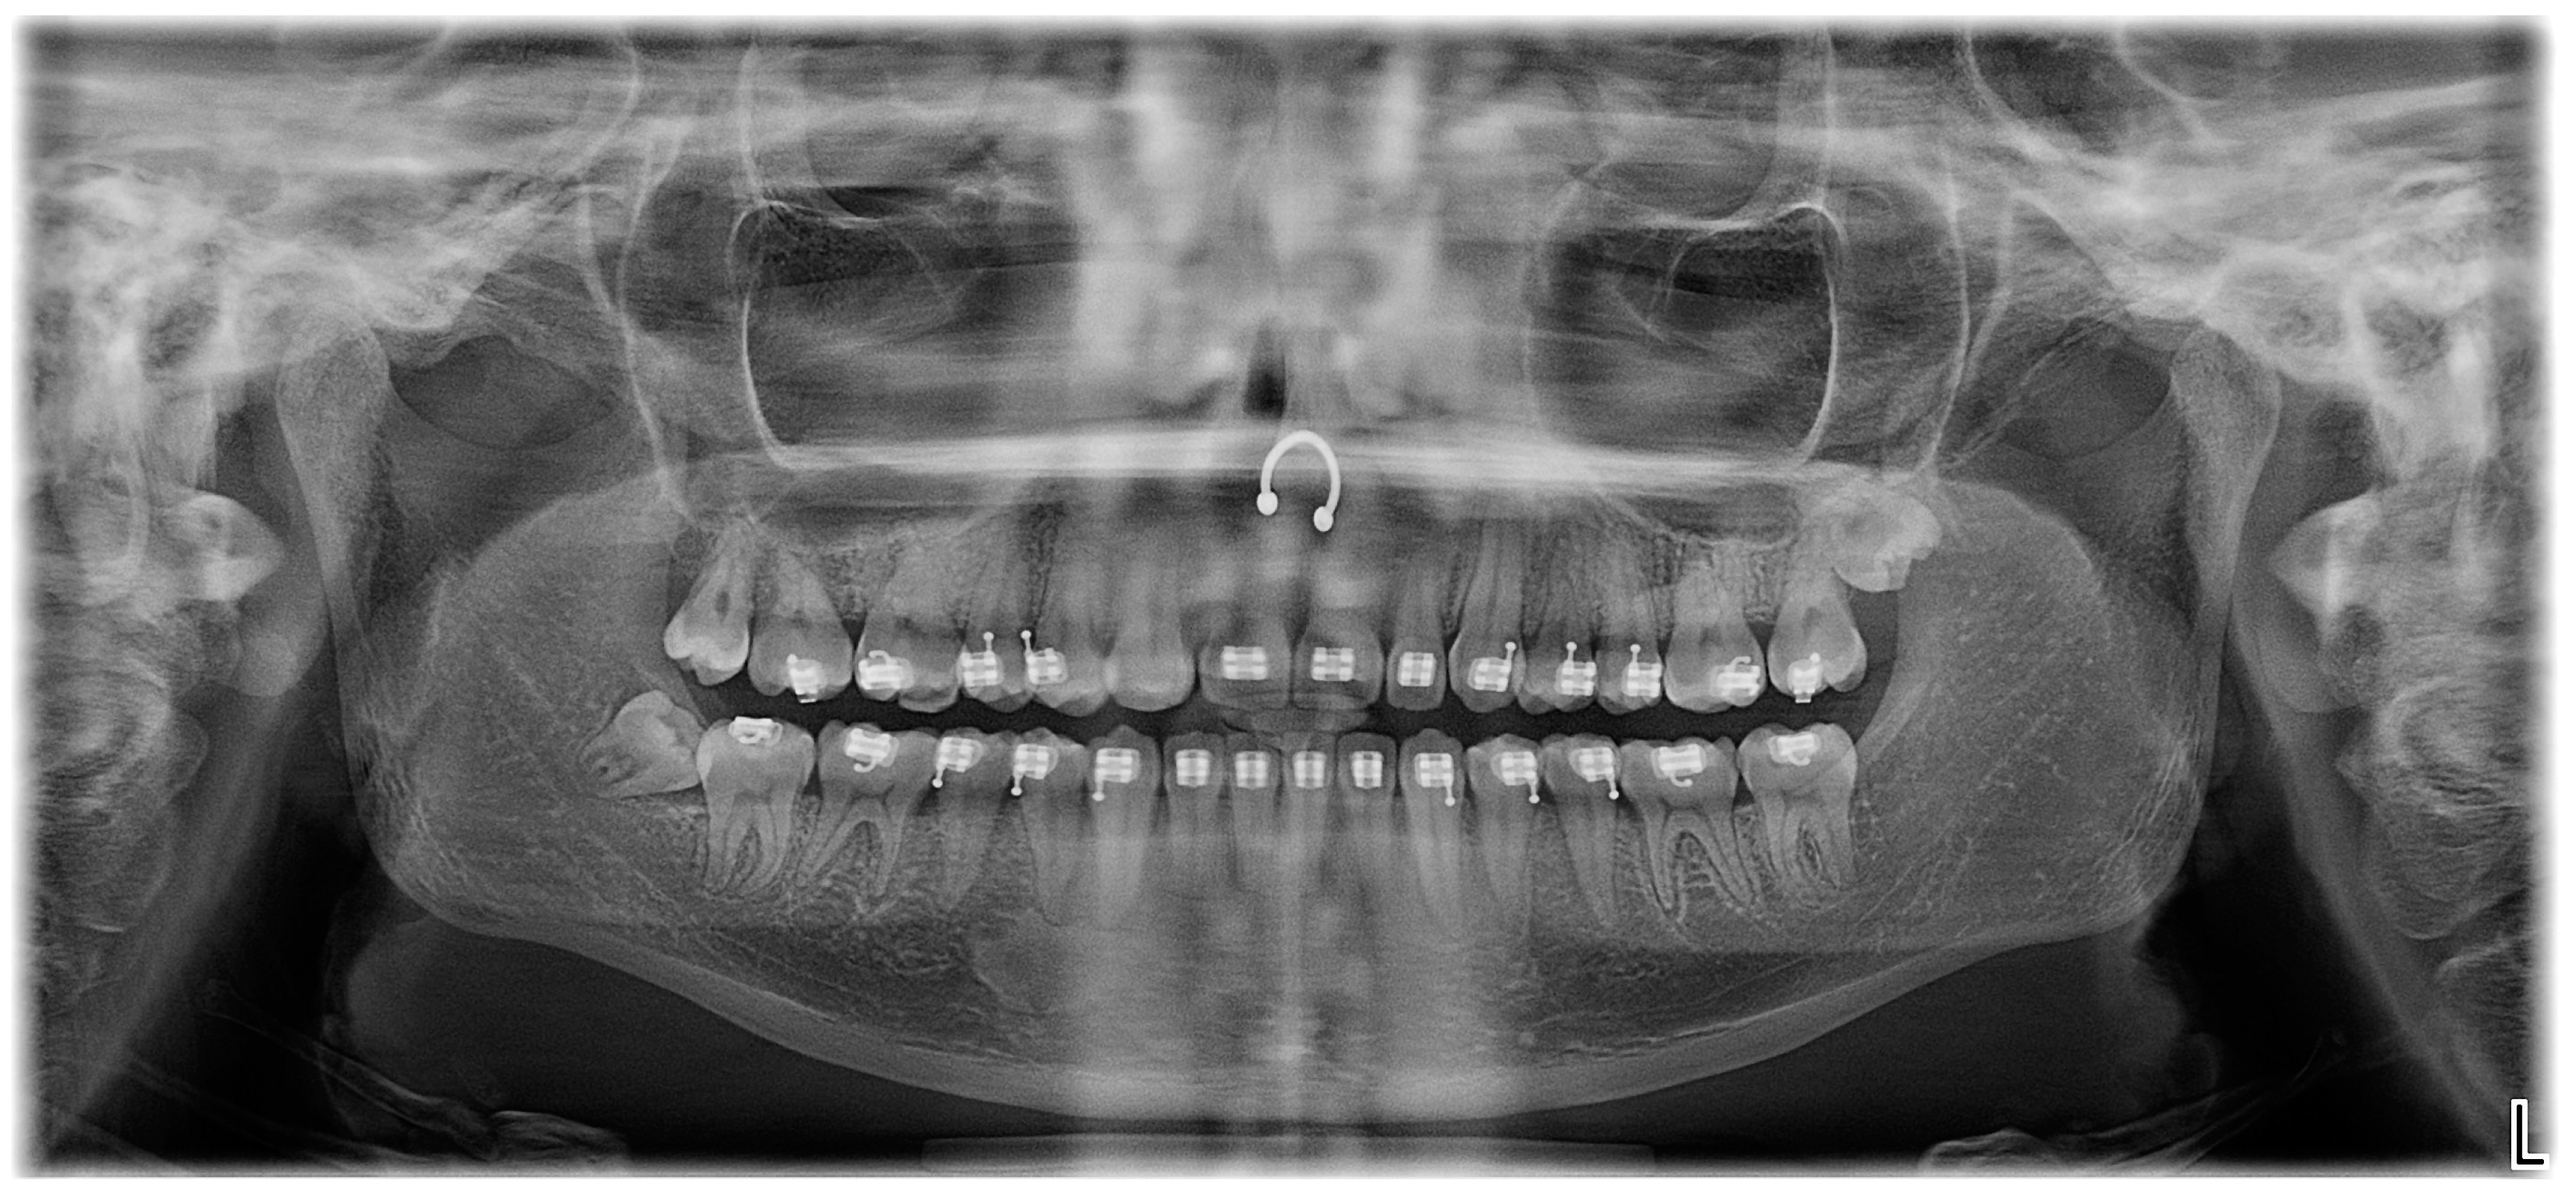

2. Case Presentation